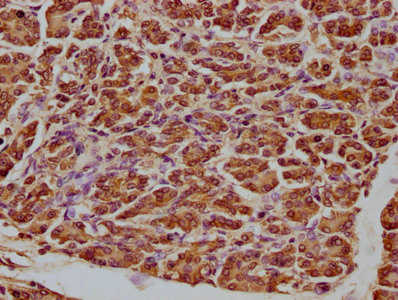

IHC image of CSB-PA002276LA01HU diluted at 1:100 and staining in paraffin-embedded human pancreatic tissue performed on a Leica BondTM system. After dewaxing and hydration, antigen retrieval was mediated by high pressure in a citrate buffer (pH 6.0). Section was blocked with 10% normal goat serum 30min at RT. Then primary antibody (1% BSA) was incubated at 4°C overnight. The primary is detected by a biotinylated secondary antibody and visualized using an HRP conjugated SP system.

IHC image of CSB-PA002276LA01HU diluted at 1:100 and staining in paraffin-embedded human cervical cancer performed on a Leica BondTM system. After dewaxing and hydration, antigen retrieval was mediated by high pressure in a citrate buffer (pH 6.0). Section was blocked with 10% normal goat serum 30min at RT. Then primary antibody (1% BSA) was incubated at 4°C overnight. The primary is detected by a biotinylated secondary antibody and visualized using an HRP conjugated SP system.